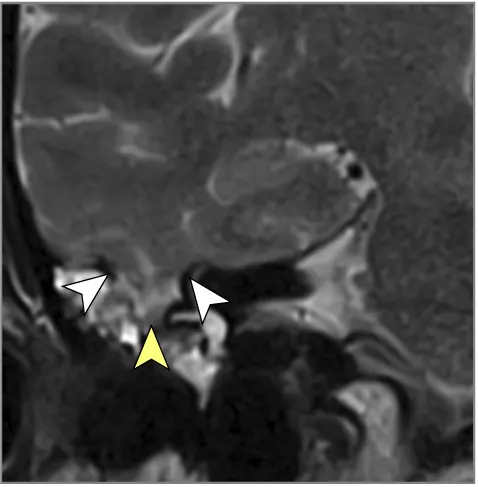

მრტ მიგნებები, რომლებიც მიუთითებს ინტრაკრანიალურ ჰიპერტენზიაზე (ხშირად ჩანს IIH-ში, მაგრამ შეიძლება მოხდეს ქრონიკული აწეული ICP-ის სხვა მიზეზებით) [9]:

- თავის ტვინის მრტ: სასურველი მოდალობა დეტალური ანატომიური შეფასებისთვის. შეუძლია აჩვენოს პარკუჭების გადიდება (ჰიდროცეფალია), გამოავლინოს ობსტრუქციული დაზიანებები (სიმსივნეები, კისტები, წყალსადენის სტენოზი), აჩვენოს მომატებული ICP-ის გართულებები (თიაქარი), აღმოაჩინოს კომუნიკაციური ჰიდროცეფალიის მიზეზები (მაგ., წინა სისხლჩაქცევის/ინფექციის ნიშნები), გამოავლინოს IIH-ის მიმანიშნებელი ნიშნები (ცარიელი კეხი, მხედველობის ნერვის გარსის გაფართოება, უკანა თვალის კაკლის გაბრტყელება, ვენური სინუსის სტენოზი MRV-ზე), ან აჩვენოს ცერებრალური შეშუპების გამომწვევი ძირითადი პათოლოგია (ინსულტი, სიმსივნე, ანთება) (7). სპეციფიკურ მიმდევრობებს (მაგ., CISS/FIESTA) შეუძლიათ შეაფასონ ლიკვორის ნაკადის დინამიკა.

| იდიოპათიური ინტრაკრანიალური ჰიპერტენზია (IIH) | თავის ტკივილი (ხშირად ყოველდღიური, პულსირებადი), პაპილედემა (ჩვეულებრივ ორმხრივი), ვიზუალური დარღვევები (გარდამავალი დაბნელება, ველის დაკარგვა), პულსირებადი ტინიტუსი, +/- CN VI პარეზი. ცნობიერების ნორმალური დონე. ტიპიურად ახალგაზრდა, ჭარბწონიანი ქალები. ნევროლოგიური გამოკვლევა სხვა მხრივ ნორმალურია (გარდა პაპილედემის/CN VI პარეზისა). | ნორმალური მრტ/კტ ტვინის სტრუქტურა (არ არის მასა/ჰიდროცეფალია). მრტ/MRV შეიძლება აჩვენოს მეორადი ნიშნები (ცარიელი კეხი, მხედველობის ნერვის გარსის გაფართოება, უკანა თვალის კაკლის გაბრტყელება, ვენური სინუსის სტენოზი). LP ადასტურებს მომატებულ გახსნის წნევას (>25 სმ წყ.სვ) ნორმალური ლიკვორის შემადგენლობით. |